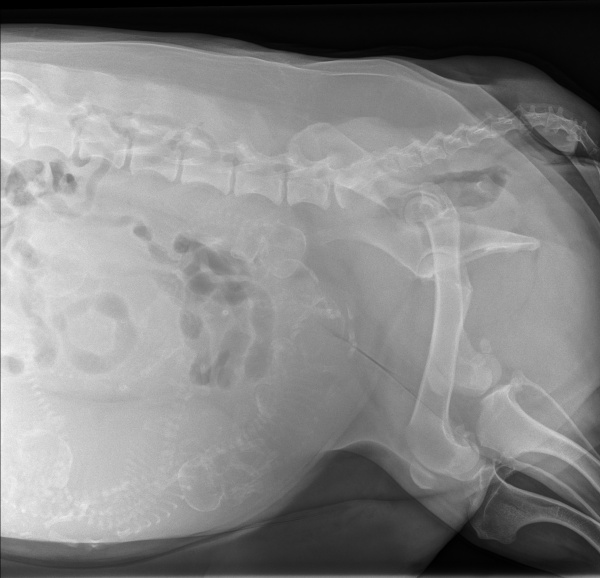

Lizzy re-presented after the unsuccessful attempt to birth at home. Ultrasound examination showed signs of fetal distress. Fetal heart rates decreased to 130-150 bpm. Radiographs showed 8-10 puppies still present in the uterus indicating a much higher risk for Lizzy and the puppies.